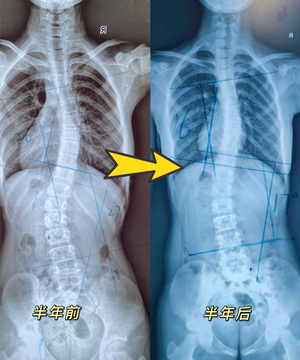

脊柱上下雙彎矯正效果

13歲女孩,2021年2月份檢查出脊柱側(cè)彎,胸26°,腰27°。制作支具后,患者沒有不舒適感,并表示愿意配合穿戴支具。每天穿戴22個(gè)小時(shí)左右,半年后,身高由150生長至153cm,脫支具24小時(shí)后拍片,側(cè)彎角度由原先胸26°,腰27°,減少至胸16°,腰17°。